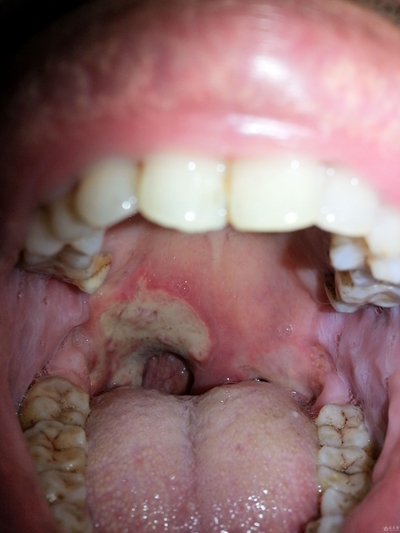

口腔癌圖片

口腔癌的前兆 (6)